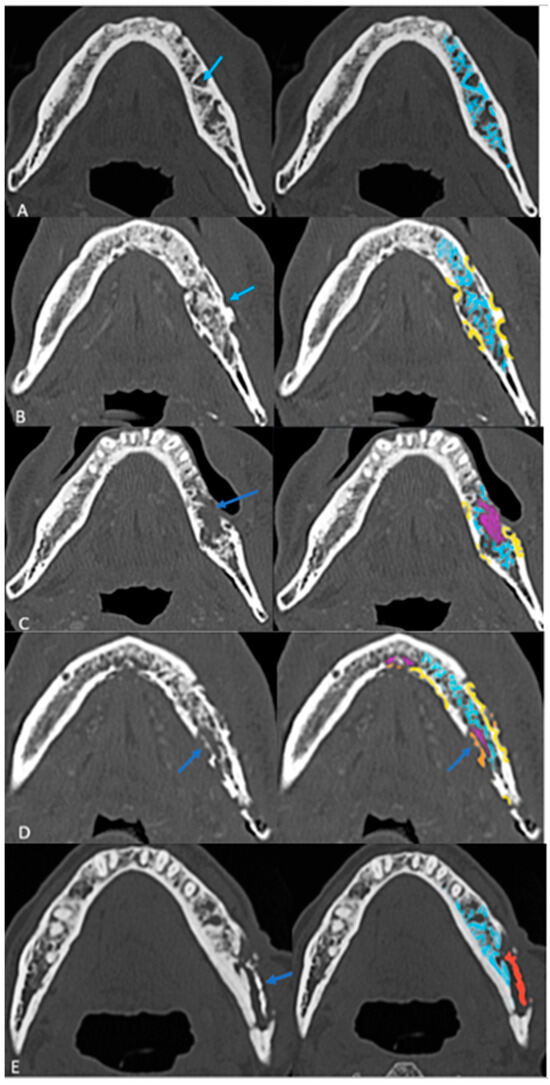

Follow-up imaging demonstrated the progression of ORN in most cases, with increased bone resorption (77%), fragmentation (92%), and sclerosis (92%). Sequestrum formation and intraosseous gas appeared in later stages, while periosteal reaction was rare (3%), differentiating ORN from osteomyelitis. Neither intraosseous gas nor orocutaneous fistulae are an indicator of severity per se. Soft tissue involvement was less than bone destruction, and its isoenhancing nature on CT helped to distinguish ORN from tumor recurrence. This analysis of radiological evolution of ORN leads us to propose a four-step grading system that builds on ClinRAD to aid in diagnosis (Figure 4A–E).

Figure 4. The proposed structured grading system of ORN on axial CT images: (A) Grade 0: Resorption (Early Stage) with thickened and sparse trabecular (blue). (B) Grade 1: Partial thickness cortical resorptions (yellow). (C) Grade 2: Full-thickness cortical resorption with medullary extension (pink areas). (D) Grade 3: Fragmentation/fracture (Orange). (E) Grade 4: Sequestrum (red) (End Stage).

Based on these findings, a structured grading system was proposed (Figure 4A–E) (Table 3).